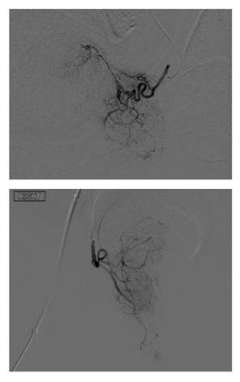

PAE Figure 1

PAE is performed with local anesthesia and mild ‘twilight’ sedation and is generally an outpatient procedure, meaning the patient will go home after the procedure. Our IR physicians will insert a small catheter (which is a thin hollow tube) into the artery of the patient’s upper thigh or wrist, and with the use of X-rays guide the catheter to the arteries supplying the enlarged prostate. Tiny particles are then injected through the catheter into the prostate arteries, reducing the blood supply. This in turn shrinks the prostate gland, which alleviates the benign prostatic hyperplasia (BPH) symptoms.